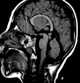

Giant cell astrocytoma

Subependymal giant cell astrocytoma (SEGA, SGCA, or SGCT) is a low-grade astrocytic brain tumor (astrocytoma) that arises within the ventricles of the brain. It is most commonly associated with tuberous sclerosis complex (TSC). [Source: Wikipedia ]